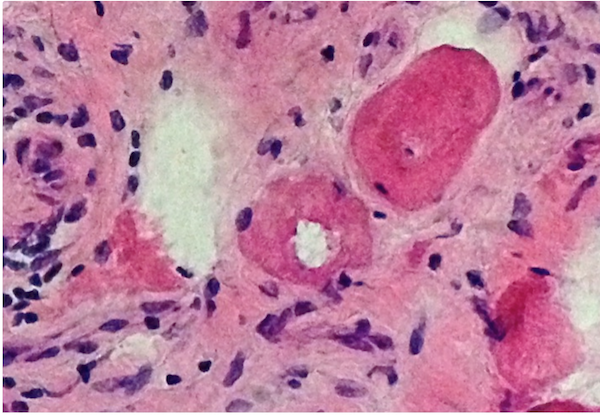

Microscopic (histologic) description

- Variation in myofiber sizes with small angulated myofibers, either individually or in groups

- Hypertrophied myofibers can also be seen

- An increase in internal nuclei (normal muscle can have up to 3% of myofibers having internal nuclei) can be seen

- There can be a brisk inflammatory response including CD8+ lymphocytes, which may invade non-necrotic myofibers

- Occasional myofibers undergoing phagocytosis by CD68+ macrophages can be identified

- The Gomori Trichrome stain shows "rimmed vacuoles", although the extent of myofibers having classic rimmed vacuoles varies (Dubowitz: Muscle Biopsy: A Practical Approach, 2013, 4th Edition)

- The vacuoles disrupt the myofiber architecture and can lack NADH-TR staining (Dubowitz: Muscle Biopsy: A Practical Approach, 2013, 4th Edition)

Microscopic (histologic) images